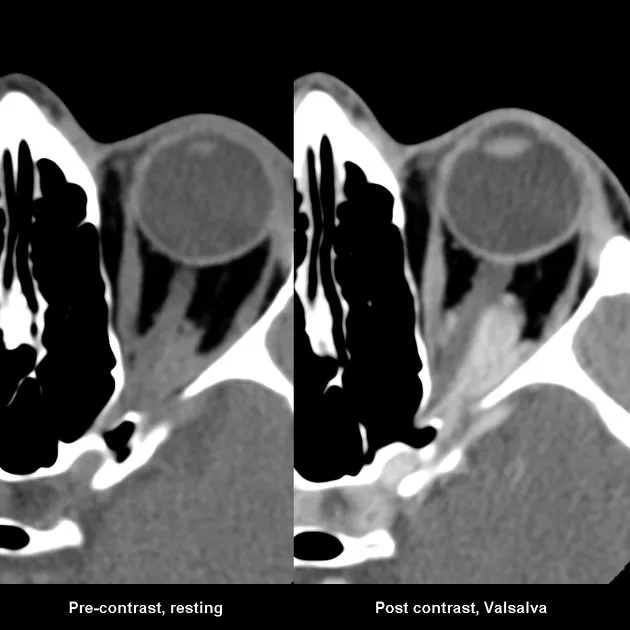

Orbital Varix (Venous Malformation)

- Low-flow venous channels; dilate with Valsalva or dependent head position.

- Key: Intermittent, non-pulsatile proptosis.

- Gaze-evoked proptosis is a classic sign.

- Imaging (CT/MRI): Shows distensible vascular channels, phleboliths may be present.

- Orbital Varix: Characterized by intermittent proptosis that ↑ with Valsalva maneuver or dependent head position; phleboliths may be present.